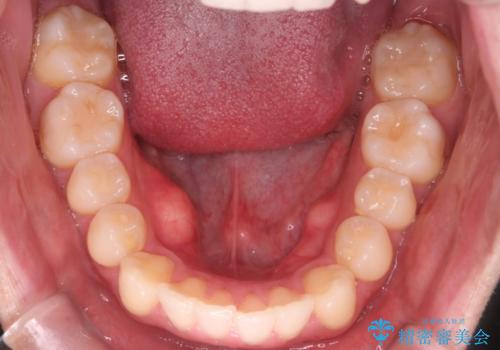

- 20代男性

- 治療期間

- 1年2ヶ月

- 上の前歯が出ているのが少し気になるとの事で来院されました。

インビザライン希望のため、IPR(歯と歯の間を削る処置)を行うことで、前歯の位置とがたつき整える治療計画を立てました。